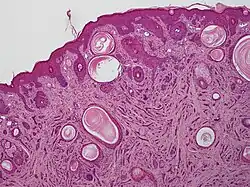

| A microscopic view of microcystic adnexal carcinoma | |